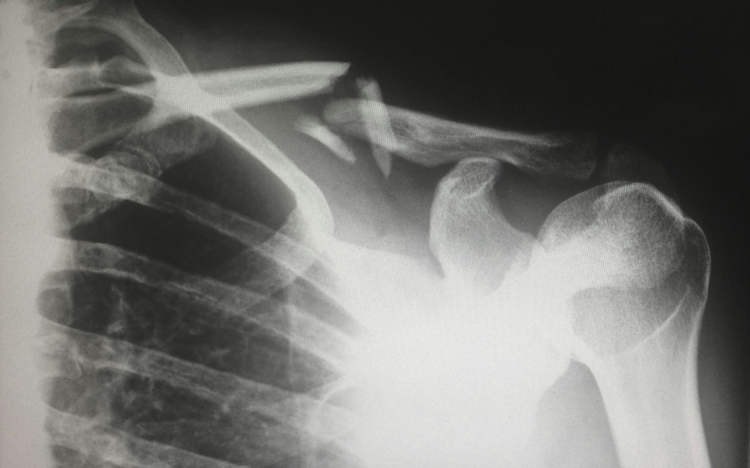

Một người phụ nữ 48 tuổi tại Thành Đô, Trung Quốc đã gây xôn xao dư luận sau khi được chẩn đoán bị gãy xương chỉ vì... xoay người trên giường. Các bác sĩ xác định nguyên nhân là do thiếu hụt vitamin D nghiêm trọng, xuất phát từ thói quen tránh nắng và sử dụng kem chống nắng quá mức suốt nhiều năm.

Theo thông tin từ Bệnh viện Y học Cổ truyền Tân Đô (XinDu), nữ bệnh nhân này chưa từng mặc áo ngắn tay hay để da tiếp xúc với ánh nắng trong suốt thời gian dài. Mỗi khi ra ngoài, bà đều bôi kem chống nắng và che kín cơ thể để tránh nắng. Kết quả kiểm tra cho thấy mức vitamin D trong máu của bà ở mức cực thấp, dẫn đến tình trạng mất xương nhanh và loãng xương nặng.

Trường hợp hy hữu này được bác sĩ Long Song chia sẻ nhằm cảnh báo cộng đồng về nguy cơ từ việc lạm dụng kem chống nắng và tránh nắng cực đoan. Bác sĩ Jiang Xiaobing, Trưởng khoa Phẫu thuật Cột sống Bệnh viện Đại học Y Quảng Châu, cho biết: "Chúng tôi thường gặp những người mặc kín mít từ đầu đến chân để tránh nắng, nhưng điều này thật sự không tốt cho sức khỏe. Toàn bộ xương trong cơ thể được tái tạo hoàn toàn sau mỗi 10 năm, nhưng từ tuổi 30, chúng ta bắt đầu mất dần khối lượng xương với tốc độ 0,5% đến 1% mỗi năm. Việc thiếu vitamin D, không tiếp xúc ánh nắng và chế độ ăn thiếu canxi sẽ cản trở quá trình hấp thụ canxi và làm tăng nguy cơ loãng xương."